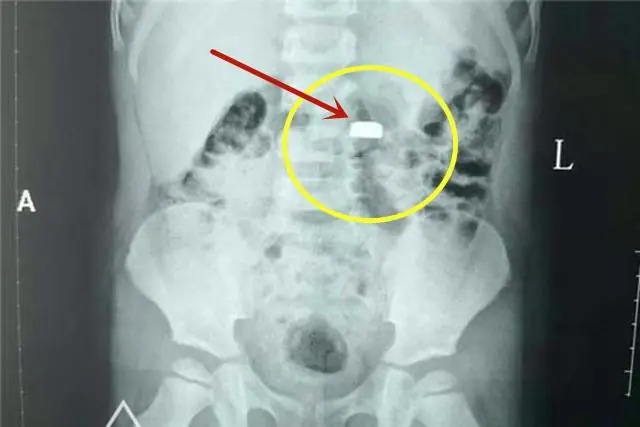

![]() |

| Viên pin cúc áo mà bé trai 3 tuổi của chị Linlin nuốt phải gây nguy hiểm dù tới bệnh viện ngay sau đó |

Quan trọng nhất, cần nhớ, dù dùng mật ong hay phương pháp sơ cứu nào cũng phải đưa trẻ đi cấp cứu càng sớm càng tốt ngay sau đó. Thông báo rõ hoặc mang theo loại pin trẻ nuốt phải. Bác sĩ sẽ sắp xếp chụp X-quang, CT và ưu tiên phương pháp nội soi để gắp pin ra sớm nhất có thể, ngăn chặn hóa chất rò rỉ phá hủy nội tạng.